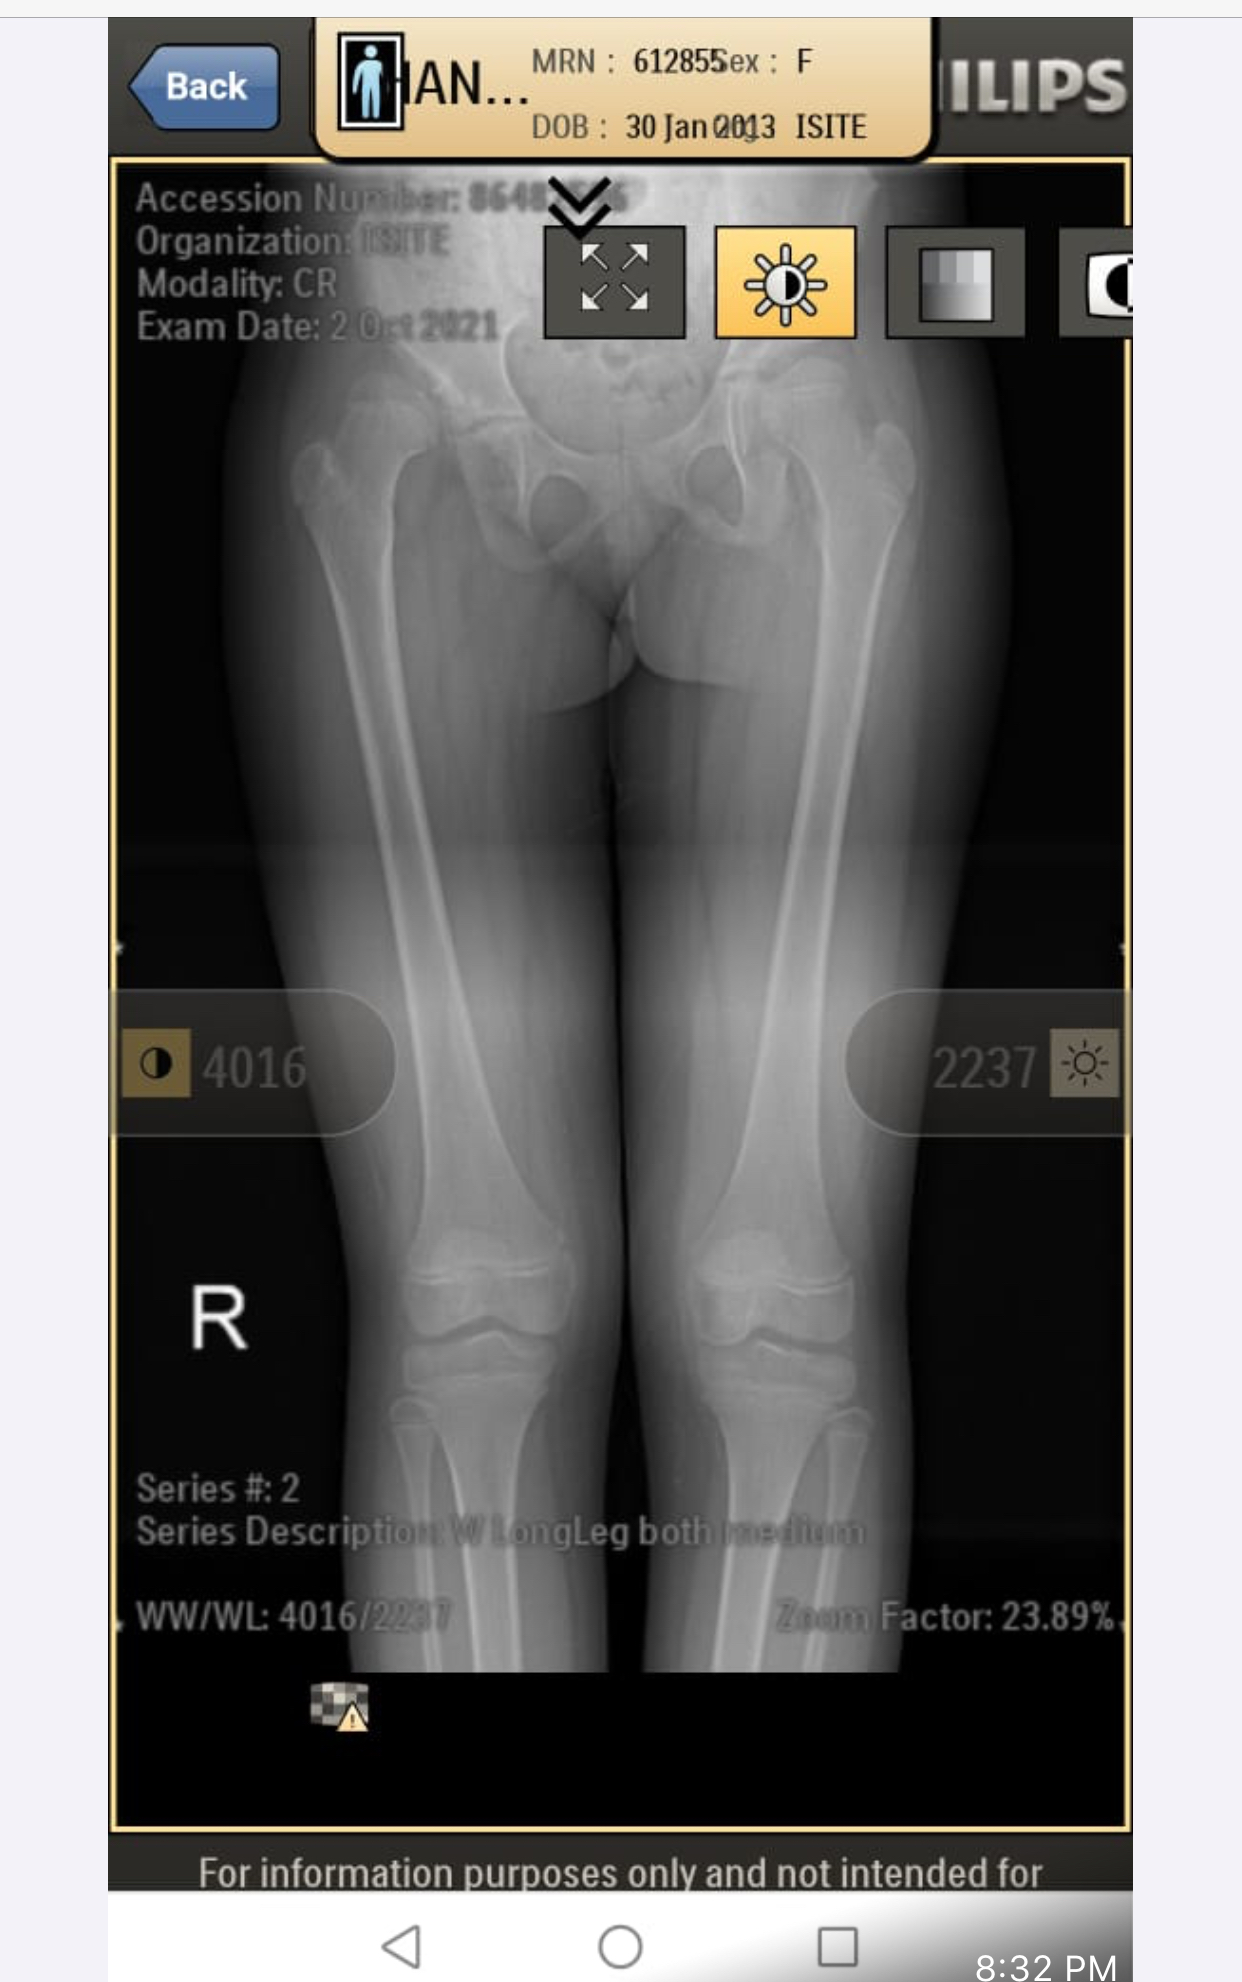

My daughter is diagnosed with hip dysplasia at age of 8.8 years. Doctor is saying for surgery immediately but we got another opinion and that surgeon is saying that there is no success rate of surgery right now. You have to wait once she grow up n then we will go for hip replacement. While the other doctor is saying that surgery is must. We need an opinion on it. Xrays are attached

She is limping on right side but she never complains pain in past. Now sometimes she complains but not frequently.

She is limping on right side. Never complained in past but after diagnosis she complains but rarely.

she definitely need surgery to keep the head at level of socket. you should consult DR. CHIRAGH at GHURKI TRUST HOSPITAL, LAHORE. He is very experienced and expert for this disease.

it needs operation as soon as possible.

Surgery at present at 9yrs of age won't result good results. And re-dislocation may occur soon after surgery. Wait for maturity and then go for translational osteotony/replacement surgery.

need surgery as soon as possible

Salam, She needs to get MRI of hip joint to measure angles related to hip dysplasia and clinical exam as well before deciding surgery. Thanks